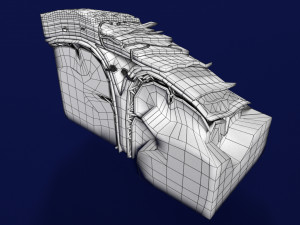

Brain with meninges scalp detailed labelled 3D 3D मॉडल

A blend model of brain along with its covering layers (meninges), skull bone and scalp labelled in detail and anatomically precise. The parts depicted are white, gray, pia, arachnoid, dura, bone, skin, fat, aponeurosis, periosteum, falx cerebri and more.

The material is high resolution image textures and normal maps based on non overlapping UVs. The texture and normal maps are packed with the blend file itself.